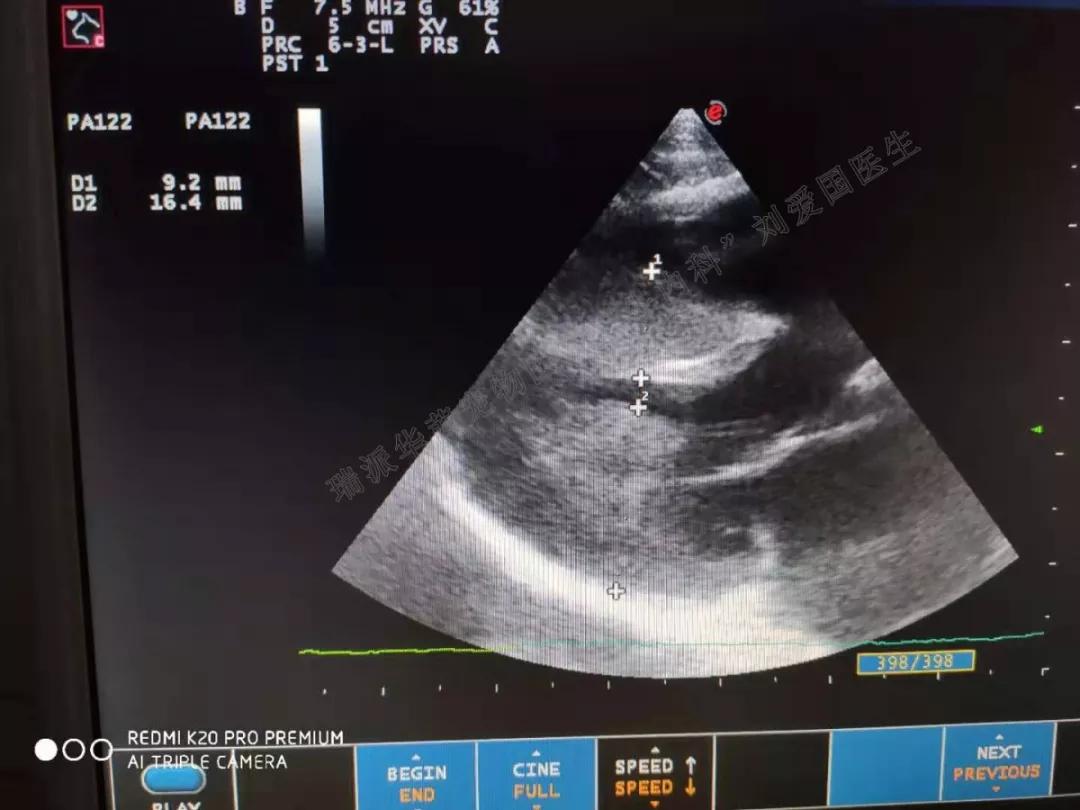

心脏超声检查

心室肥厚,室间隔不对称性增厚,也可仅有心尖部或乳头肌增厚,一般最后才出现左室后壁和二尖瓣下方室间隔增厚,目前多以后壁和室间隔厚度大于6mm为诊断猫肥厚性心肌病的标准。心室收缩末期和舒张末期内径均变小,E波变小,小于A峰,左室流出道狭窄时血流速度加快,大于1.4m/s,可见SAM现象,左心房因继发二尖瓣关闭不全而扩大,左心耳区可见血栓,有些可见心包积液或胸腔积液。